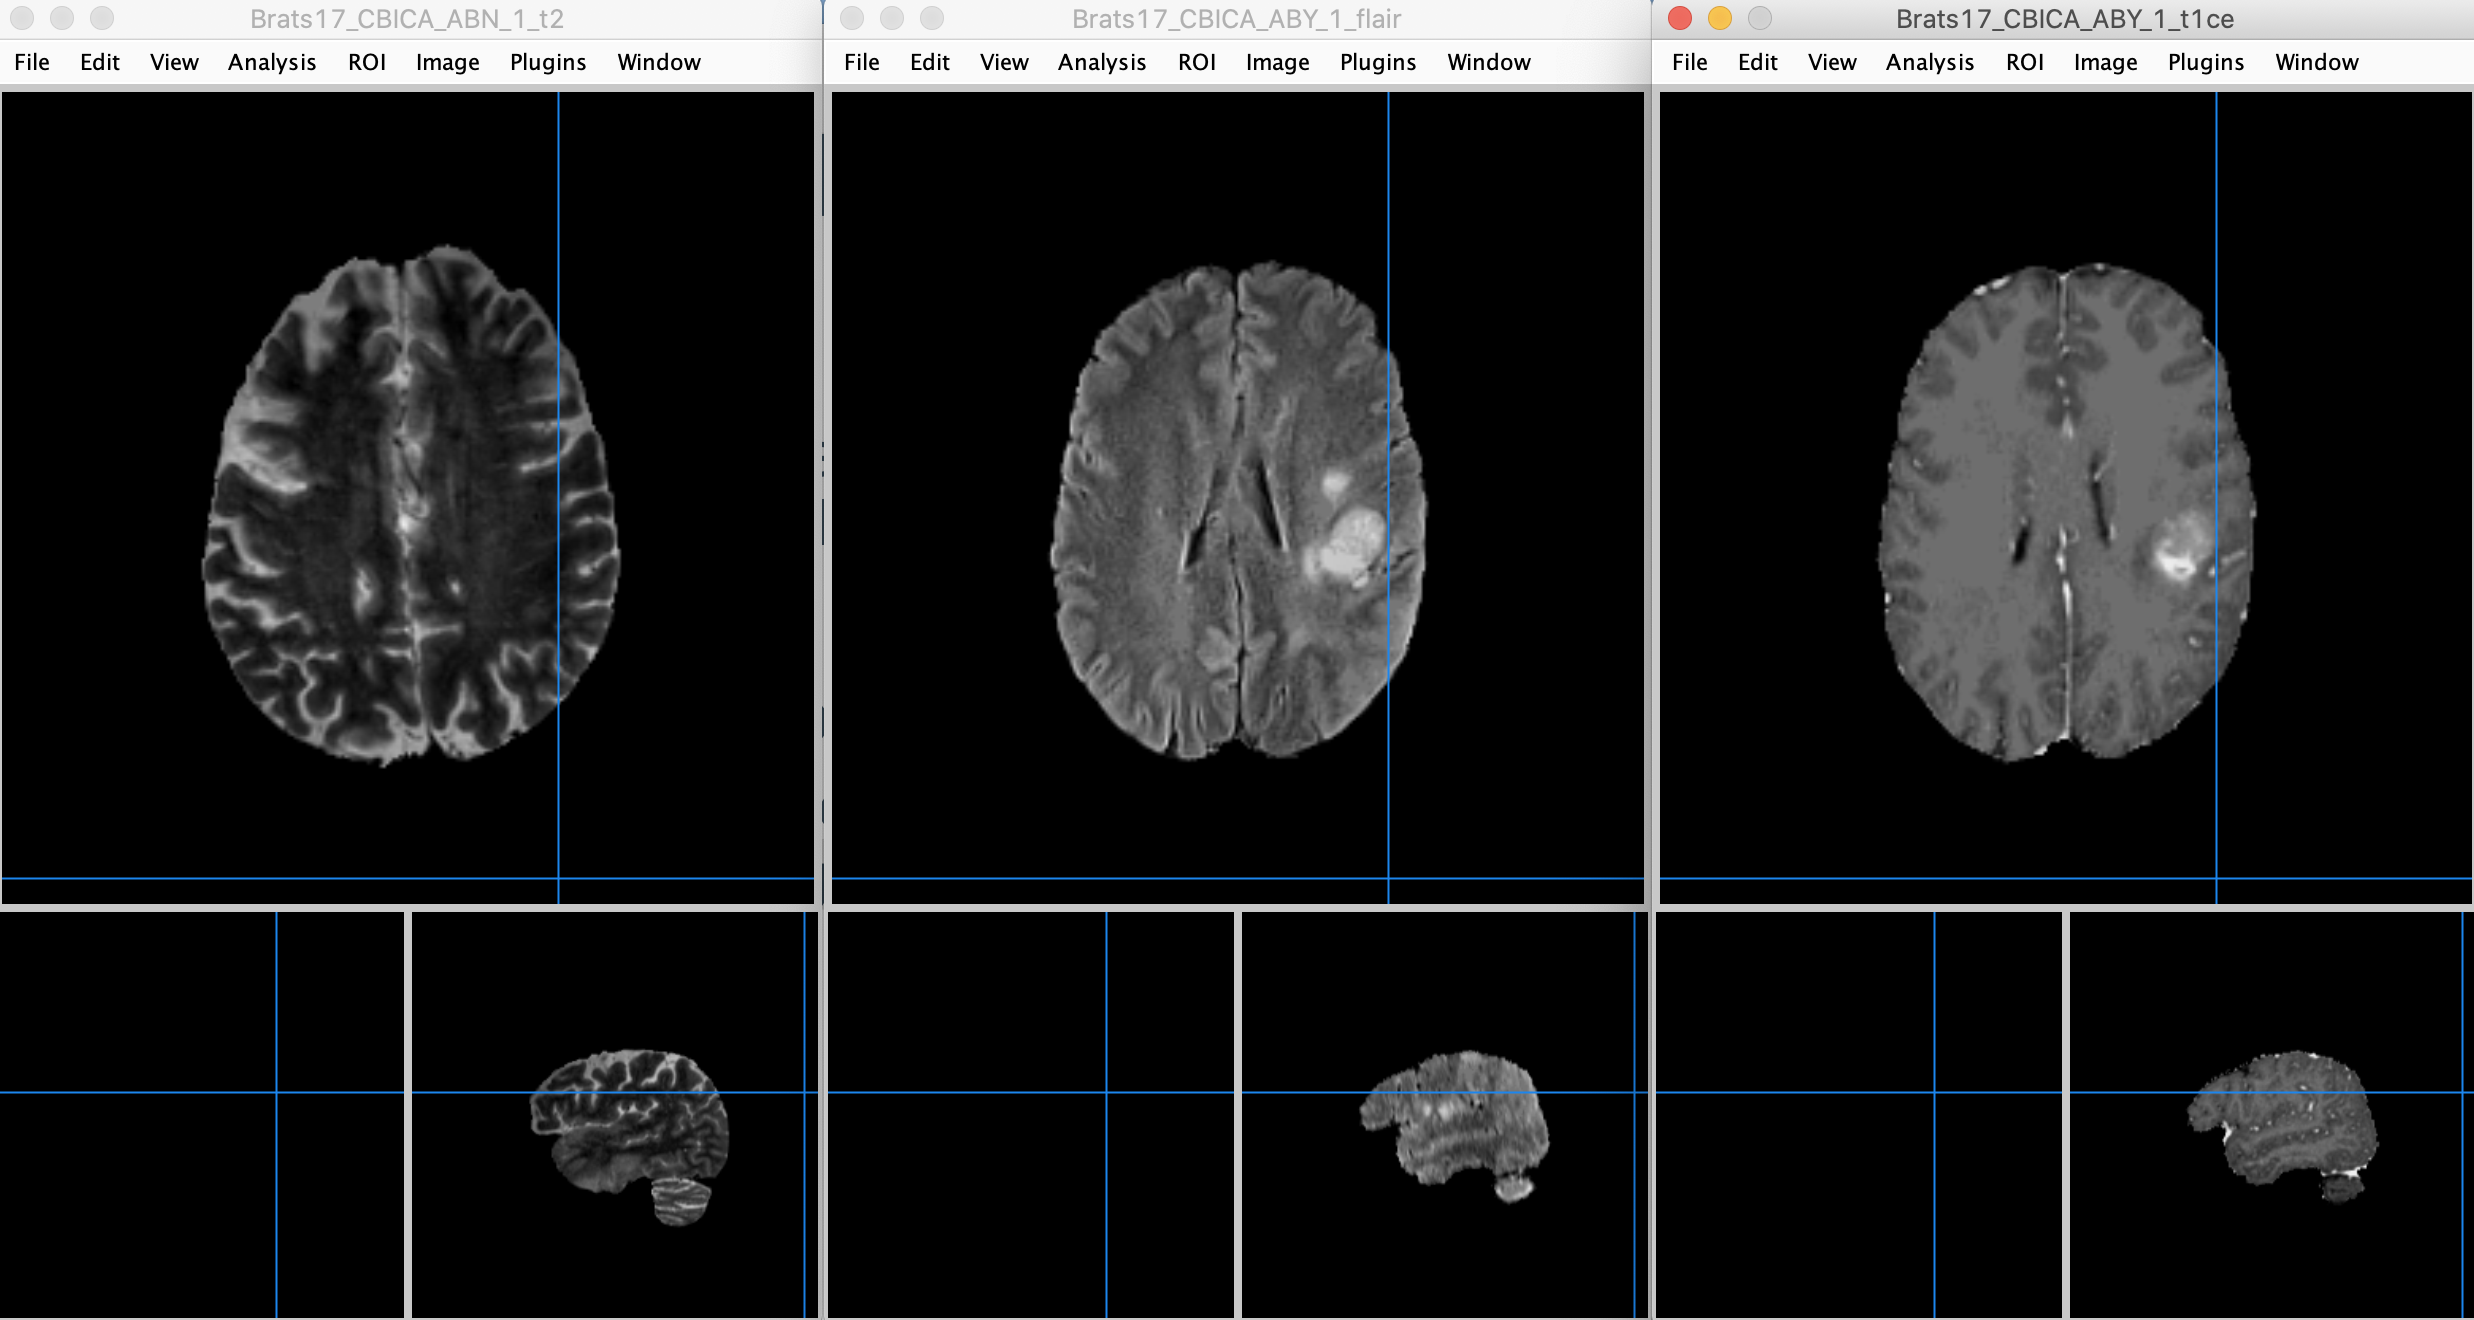

可以看到,使用SynthStrip工具可以正确去除T1、T2、FLAIR、T1CE四个序列MRI图像中的颅骨部分,解决了原有工具难以对T2、FLAIR、T1CE自动去颅骨的问题。